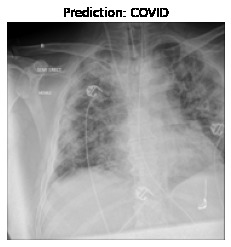

Currently, there is an urgent need for efficient tools to assess the diagnosis of COVID-19 patients. In this project, we propose a constructive solution for detecting and labeling infected tissues on CT lung images of such patients. To cut down false positives our model is trained on 4 types of lung CT images : COVID, Viral Pneumonia, Lung Opacity and normal images to get the best possible results with highest accuracy.

We built it using Tensorflow 2.x using Python. We have developed a Convolutional Neural Network model with an average accuracy of more than 85%.

We learned that COVID-19 can be succesfully detected through LUNG-CT images instead of tedious tests like Reverse transcription polymerase chain reaction (RT-PCR) which takes almost 5 hours and Rapid detection tests which has a low accuracy.

Our model contains the best of both worlds with quick detection and high accuracy.